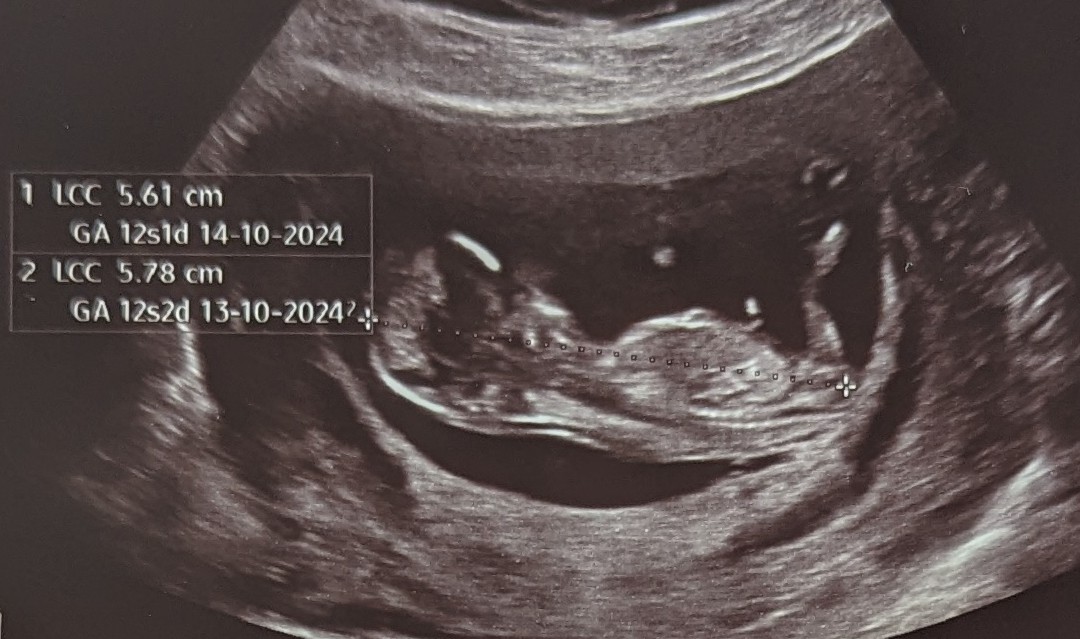

Alt så bra ut, som det skulle! Nakkefold på maks 1,5 mm, noe som er veldig bra. 2 armer og 2 ben, og en liten sprellende knopp der inne

Målt til å være 12+1 eller 12+2, så jeg fortsetter med tellingen som før.

Gynekologen gjettet med 80% sikkerhet på at det er en liten gutt